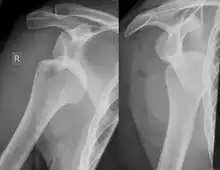

Hill–Sachs lesion post-shoulder dislocation

X-ray at left shows anterior dislocation in a young man after trying to get up from his bed. X-ray at right shows same shoulder after reduction and internal rotation, revealing both a Bankart lesion and a Hill-Sachs lesion.

Diagnosis can be suspected by history and physical examination which is usually followed by imaging. Because of the mechanism of injury, apprehension of anterior dislocation is common with provocative maneuvers. Hill–Sachs lesions have been classified as "engaging" or "non-engaging", with engaging lesions defined by the ability of the glenoid to sublux into the humeral head defect during abduction and external rotation. Engaging dislocations have a higher risk of recurrent anterior dislocation, and their presence can help guide surgical management.[2] Imaging diagnosis conventionally begins with plain film radiography. Generally, anteroposterior (AP) radiographs of the shoulder with the arm in internal rotation offer the best yield while axillary views and AP radiographs with external rotation tend to obscure the defect. However, pain and tenderness in the injured joint make appropriate positioning difficult and in a recent study of plain film x-ray for Hill–Sachs lesions, the sensitivity was only about 20%. i.e. the finding was not visible on plain film x-ray about 80% of the time.[3]